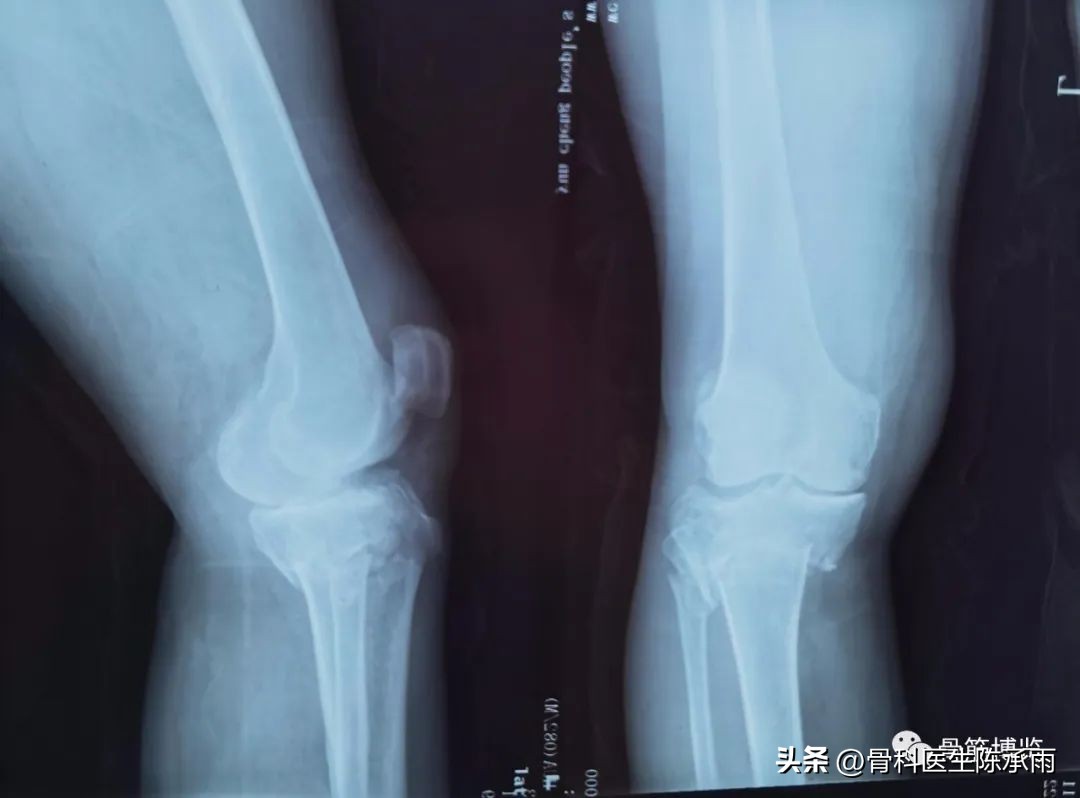

近段时间的胫骨平台骨折,没来得及详细整理

胫骨平台骨折的分型比较多,我们临床上常用的就是Schatzker分型和AO骨折的分型,还有骨折脱位的Hohi-Moore分型,这是我们常用的三个分型。